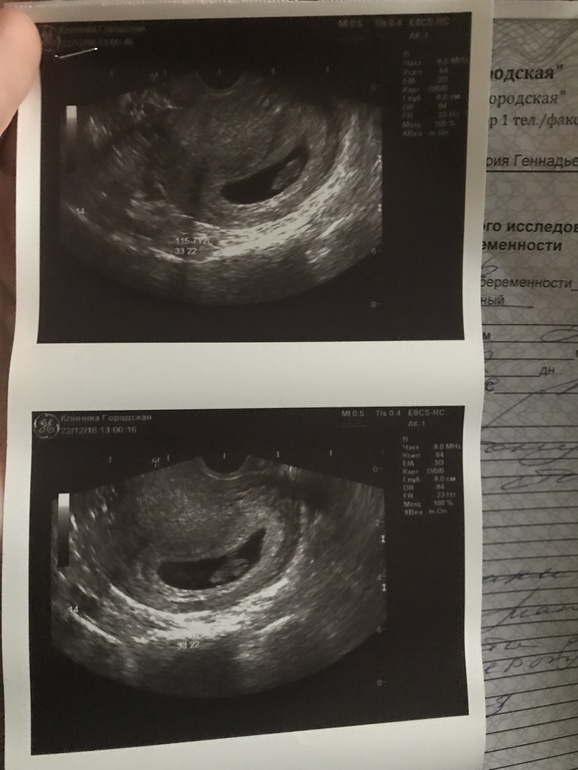

Болит живот и поясница, тонус, треникиПошла сегодня на узи, так как тянуло живот всю ночь. Показало гипертонус задней стенки. Врач сказал пить Магний 3 раза в день по одной таблетки. Лежу целый день, а живот прям тянет сильно, такого раньше не было. Стоит ли мне самой себе назначить еще папаверин? Если да, то в каких дозах и сколько дней принимать?